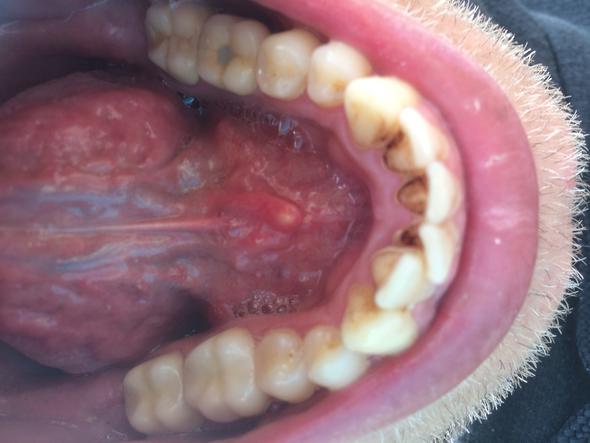

Ein Belag auf der Zunge und weiß gefleckte und/oder gerillte Fingernägel gelten gemeinhin als Symptom für ein angeschlagenes Immunsystem. Denn auch auf deine Zunge kann sich ein Belag festsetzen. Veränderungen in Form, Farbe, Textur oder Belag können Hinweise auf verschiedene Störungen im Organismus sein.

Normalerweise zeigen sich die Beläge aber nicht nur an der Zunge, sondern auch an anderen Schleimhäuten.

Diese kann auf die Zunge beschränkt sein, aber häufiger ist es ein Ausdruck einer anderen zu Grunde liegenden Erkrankung, bei der die Flecken auf der Zunge nur ein. Schrubb den Belag mit der Zahnbürste Es gibt eine sogenannte Landkarten-Zunge (lingua geographica exfoliativa). Zahnbelag, oberflächliche Schicht auf den Zähnen.